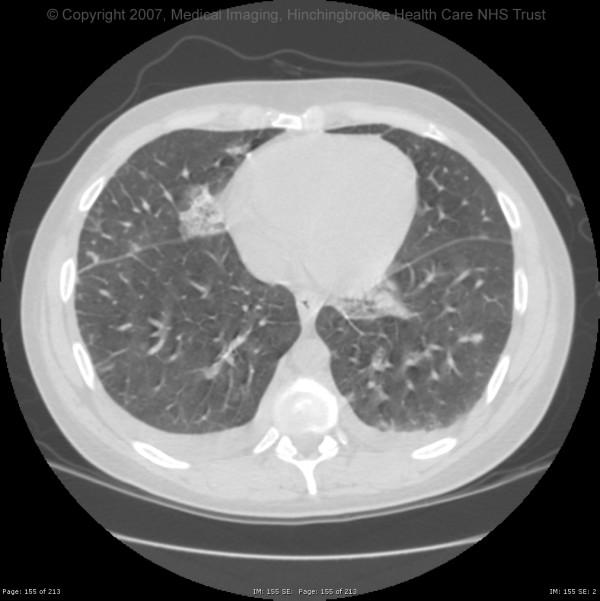

A 37-year-old male intravenous drug user was admitted with pain in his right groin, fever, rigors and vomiting following a recent injection into the right femoral vein. Admission blood cultures grew Fusobacterium nucleatum, Solobacterium moorei and Bacteroides ureolyticus. The patient was successfully treated with intravenous penicillin and metronidazole.

This case report describes an unusual case of femoral thrombophlebitis with septic pulmonary embolism associated with anaerobic organisms in a groin abscess. Solobacterium moorei, though rarely described, may also have clinically significant pathogenic potential.